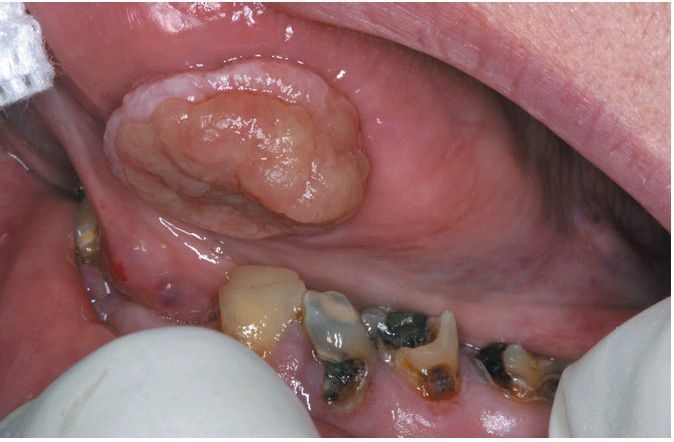

Traumatic Granuloma.

Exophytic ulcerated mass on the ventrolateral tongue associated with multiple jagged teeth.